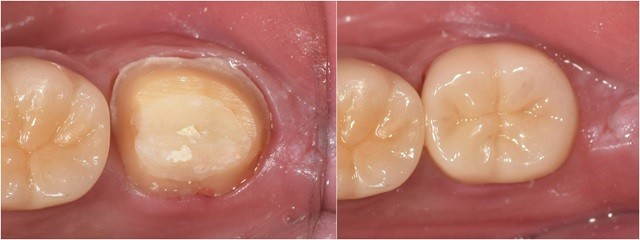

신경치료를 받은 치아는 내부 구조가 약해져 쉽게 깨질 위험이 큽니다. 따라서 치아 강도를 보강하고 장기적인 구강 건강을 유지하기 위해 크라운을 씌우는 과정이 필수적입니다. 크라운 치료가 안정적으로 자리 잡으려면 ‘레진코어’라는 보강 과정이 반드시 선행되어야 합니다.

신경치료는 치아 내부의 감염을 제거하고 신경관을 밀봉하는 치료입니다. 그러나 신경치료 후 치아 내부가 비어 있는 상태가 되면 구조적으로 매우 취약해지고, 외부 충격에 쉽게 손상될 가능성이 커집니다. 이를 보완하기 위해 시행하는 과정이 바로 레진코어입니다. 레진코어는 치아 내부의 빈 공간을 생체친화적인 복합 레진으로 채워 강도를 보강하고, 크라운이 안정적으로 고정될 수 있도록 돕는 역할을 합니다. 단순히 공간을 메우는 것이 아니라, 크라운 치료의 성공을 보장하고 치아의 장기적인 건강을 유지하는 핵심적인 단계인 것이죠.

크라운 치료 성공, 레진코어가 좌우한다

크라운 치료는 단순히 치아를 덮는 치료가 아닙니다. 치아 내부 구조를 복원하고 안정적인 기반을 제공하는 레진코어가 선행되어야 크라운이 제 역할을 다할 수 있습니다. 이를 통해 치아의 강도를 높이고, 오랜 기간 동안 건강한 치아 상태를 유지할 수 있습니다. 정기적인 치과 점검과 관리로 치료 후에도 구강 건강을 유지하는 것이 중요합니다.

레진코어는 단순한 보조 과정이 아닌, 크라운 치료의 성공을 위한 필수적이고 결정적인 단계임을 꼭 기억하길 바랍니다.